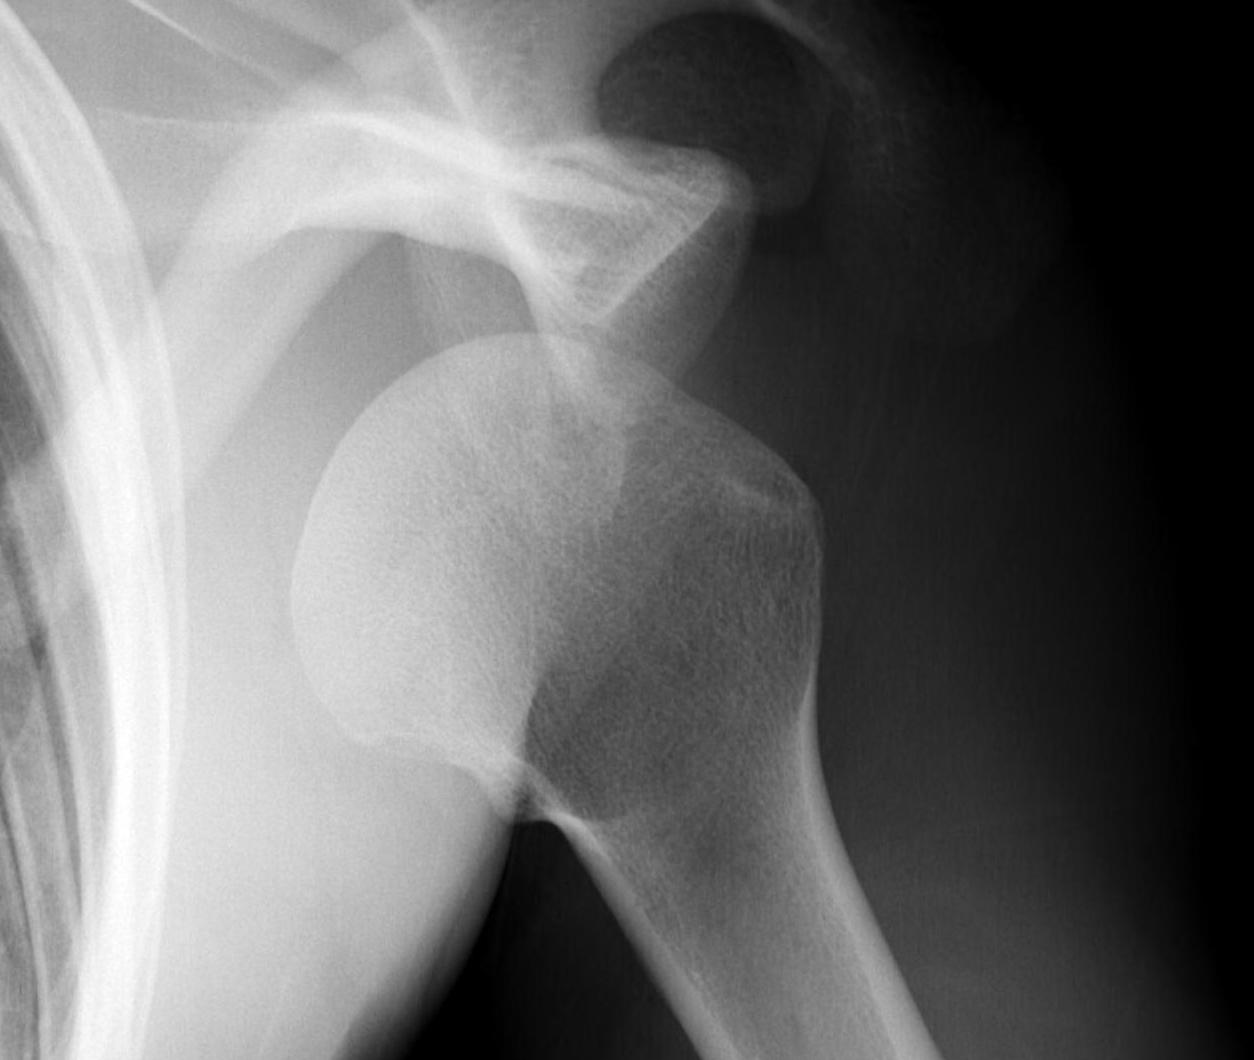

Xray

True AP

Scapular Lateral

Axillary Lateral

Garth (aim beam caudally)